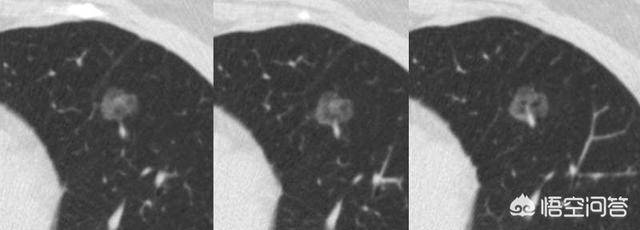

La flèche pointe vers le nodule, qui était très petit lorsqu'il a été découvert en mars 2016, environ 0,5 cm, et maintenant les examens médicaux de routine révèlent de très nombreux nodules comme celui-ci.Il n'existe aucun moyen de déterminer s'il s'agit d'une tumeur bénigne ou maligne sur les images, seule l'option de l'examen, et l'examen et le suivi constituent également le meilleur outil.

Sept mois plus tard, lors du deuxième examen de suivi en octobre 2016, il était évident que ce nodule était devenu plus grand et plus rond. Le nodule élargi lors du suivi devait alerter sur la possibilité d'une tumeur maligne, mais cette patiente n'a toujours pas opté pour la chirurgie.

Après encore 1 an et 2 mois, le troisième examen en décembre 2017.Vous pouvez voir que ce nodule est beaucoup plus grand qu'avant, les signes malins sont lobulés et il est devenu solide à l'intérieur, ces signes diagnostiquent le cancer du poumon fondamentalement, mais le patient n'a toujours pas été opéré.

L'étape suivante consiste à déterminer la nature bénigne ou maligne des nodules pulmonaires. Les nodules bénins ne sont en aucun cas des ganglions lymphatiques dans les poumons, des tumeurs difformes, des pneumocytomes sclérosants, etc. Les nodules restants sont ceux qui peuvent être bénins ou malins, et le principe général du traitement de ces nodules est de recommander un suivi, avec un délai de révision allant de 3 mois à 1 an, en fonction des spécificités du nodule (morphologie, taille, densité, etc.). Certains nodules peuvent se résorber et disparaître au cours du suivi, comme les nodules inflammatoires, tandis que d'autres peuvent rester inchangés, comme les granulomes, ce qui est une bonne information. Si des signes de malignité apparaissent au cours du suivi, tels que l'élargissement du nodule, l'augmentation des composants réels ou solides dans le nodule de verre dépoli, un nodule plus dense, ou la présence de vaisseaux sanguins périphériques qui se développent, etc. En fait, c'est comme regarder les gens, un visage de droiture est généralement une bonne personne, une mauvaise personne féroce et vicieuse, et certains temporaires ne peuvent être vus que par l'observation du comportement de la personne, si les règles ne sont généralement pas effrayées, et si vous trouvez qu'il y a un mauvais comportement devrait être traité en temps opportun. Figure 1, nodule de verre dépoli dans la partie supérieure du poumon gauche (flèche orange), suivi pendant plus de deux ans sans changement. Figure 2, deux petits nodules de verre dépoli dans la partie supérieure du poumon droit (flèches orange), qui ont disparu après deux ans. Figure 3, nodule en verre dépoli dans la partie supérieure droite du poumon, qui a grossi au cours du troisième suivi, il est recommandé de le traiter positivement, et la pathologie chirurgicale du carcinome in situ, c'est-à-dire des lésions précancéreuses, peut réellement tuer le cancer du poumon dans l'œuf.

En parlant de nodules, examinons d'abord un cas de petits nodules dans les poumons. Le patient avait un rhume et une toux et un examen par scanner thoracique a révélé un nodule en verre dépoli dans le poumon droit, et une image en coupe du lobe supérieur droit du poumon avec une épaisseur de couche de 1 mm a montré un nodule partiellement solide d'une taille de 6 mm, sa partie solide (flèches) étant inférieure à 4 mm. les bords étaient clairs, et le patient a été considéré comme inflammatoire au vu de ses antécédents médicaux, et un examen de l'inflammation a été recommandé.

Les images tomodensitométriques de suivi à 3 mois ont montré une résolution complète de la lésion, compatible avec une étiologie bénigne.